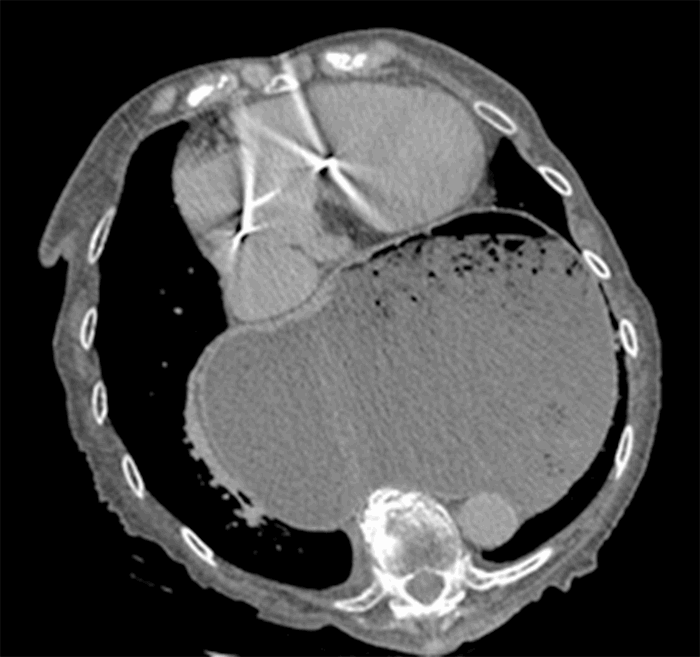

Computed tomography (CT) from outside facility performed earlier in the week revealed gastric outlet obstruction (GOO) caused by a massive type III PEH (Figure 1–4). She was subsequently discharged from this facility as she did not want surgical intervention and opted for hospice care. She presented to the ED later that week for persistent pain. At this time, it was decided to obtain a barium swallow instead of the repeat CT, demonstrating an intrathoracic stomach with concern for underlying gastric volvulus (Figure 5). Due to worsening obstructive symptoms, pain, and evidence of gastric outlet obstruction with possible gastric volvulus, it was recommended she undergo surgical intervention that day.

Figure 4. CT transverse abdominal view.